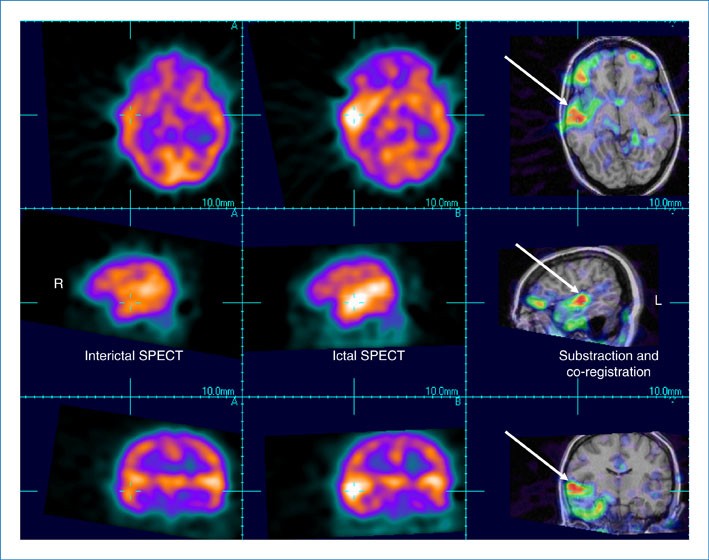

Focal Seizures With Auditory Hallucinations | SpringerLink

Focal Seizures with Auditory Hallucinations | SpringerLink link.springer.com

auditory hallucinations focal seizures figure